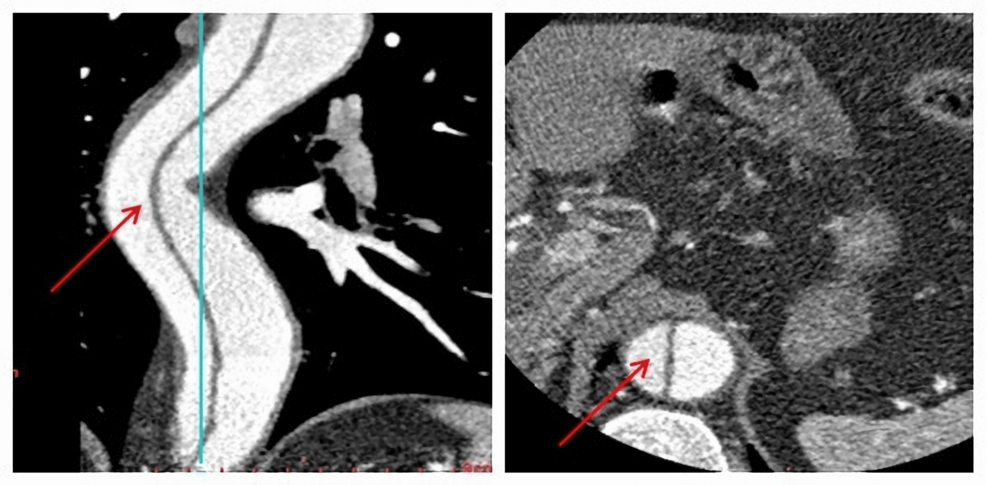

Aortic dissection, a life-threatening condition involving a tear in the inner layer of the aorta, requires careful consideration when planning any surgical intervention. Type B aortic dissections, specifically, affect the descending aorta. While laparoscopic surgery is often favored for its minimally invasive nature, the potential for hemodynamic instability during the procedure necessitates a tailored anesthetic approach. The case report details a strategy focused on maintaining stable blood pressure and heart rate throughout the operation, ultimately leading to a positive patient outcome.

The case report emphasizes the importance of a thorough pre-operative evaluation, including detailed imaging studies to assess the extent of the dissection and identify any potential complications. This assessment informs the selection of appropriate anesthetic agents and monitoring strategies.